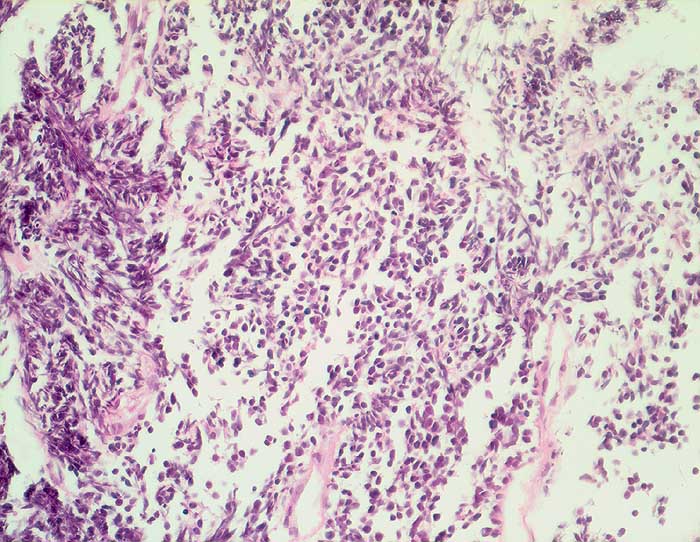

PathoPic ID 6344 - Kleinzelliges Karzinom

Kleinzelliges Karzinom

maligner Tumor

Bronchus

Lunge, Mediastinum mit Thymus

Rasen kleiner nacktkerniger Tumorzellen mit ausgeprägten Quetschartefakten aufgrund fragiler Kerne.

Tumor im Lungenmittellappen

Histologie

400